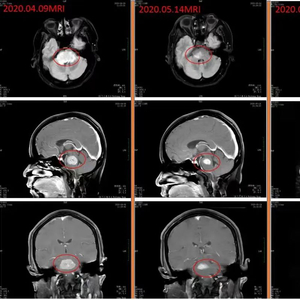

治疗1个月后,返院复查头颅MRI时,莫女士的脑干病灶已经缩小了一大半,症状已基本消失,能够生活自理了。

2020年7月,莫女士第2次复查时,脑干的病灶几乎完全消失